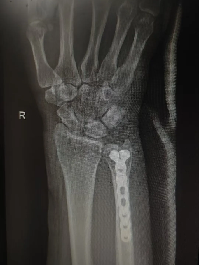

近日,来自云南昆明的自驾游游客杨女士在四川省小金县境内遭遇交通事故,致其右侧尺骨及左手小指骨折。接诊后,小金县人民医院快速响应、精准施救,成功为其实施骨折复位内固定手术。紧急救治,不仅彰显了小金县基层医疗服务的硬实力,更生动诠释了“各民族像石榴籽一样紧紧抱在一起”的深厚情谊,让民族团结之花在雪山脚下绚烂绽放。

针对杨女士伤势,小金县人民医院以“患者为中心,安全至上”为原则,迅速组建专项医疗小组,为杨女士量身定制手术方案。从术前检查、麻醉评估到器械准备,各环节精益求精。随后,骨科专家团队顺利实施骨折复位内固定手术,全程精准高效,术后杨女士生命体征平稳,手臂功能恢复良好。“留在小金县治疗,是我们最正确的决定!”康复期间,杨女士由衷感慨。她表示,医护人员不仅技术精湛,服务更贴心周到,“就像亲人一样”,既免去了长途奔波的煎熬,又节省了大笔开支,“在异乡真切感受到了各民族一家亲的温暖”。